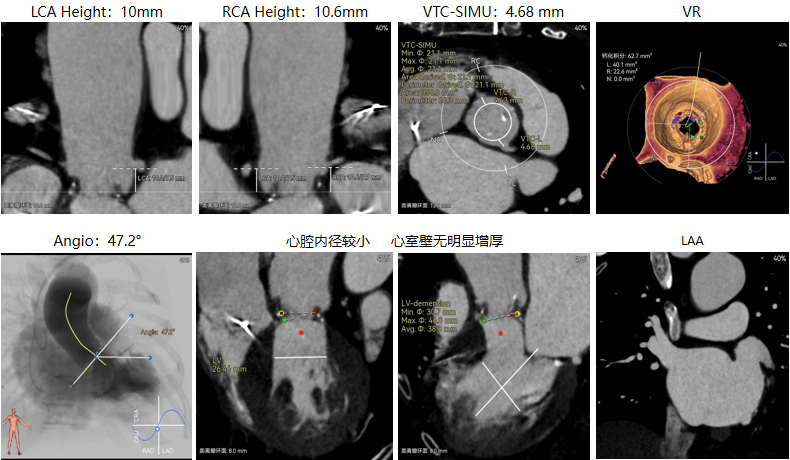

修建成教授 南方医科大学南方医院(点击查看专家详细简历) 直面瓣膜衰败,选对每一步护心路:前不久的ESC会议重磅发布瓣膜指南更新,将TAVR的患者年龄下调到70岁,且整体治疗理念迈向终身管理。该患者经历过一次外科手术,在人生70岁的当口,因生物瓣衰败再度面临 “心” 之困境,选择总是人生的一个重要课题,患者需要更微创的疗法、更耐久的瓣膜,医学的进步都是在主动探索中往前推进的,我们遵从患者的选择,不再被动应对衰败,而是主动定义瓣膜生命周期的边界。 手术一切按照既定的预演完成,术后患者情况良好,这不仅是一台手术的成功,更是将复杂瓣膜治疗推向 “精准化、耐久化” 新境序章,从瓣膜释放的瞬时血流动力学到远期抗钙化性能的预判,每一个参数都在诉说对长效生存的敬畏! 崔凯教授 南方医科大学南方医院(点击查看专家详细简历) 万千临床难题,唯提纲挈领方得始终:生物瓣衰败、心脏腔室小,这些问题都给手术添了不少难点。我始终觉得,需根据患者情况定手术方案,选择最合适的器械,综合考量:全新上市的预装干瓣开启了瓣膜心时代,预装技术让瓣膜装配标准化,规避了装载可能存在的肉眼不可见的损伤,干式储存技术规避了传统湿瓣的储存条件的钙化源头。可以说,为瓣膜的耐久性本身又增添了砝码。 对于衰败后的70岁患者,需要考量其长期耐久性问题,全新的产品需提前熟悉其产品特性;实践创新是心里装着对生命的敬畏,才能在复杂手术里找到办法。手术刀处理的不只是病,更是在跟时间赛跑,帮患者找希望。我们始终在找能让患者长期好好活下去的最好办法! 患者病史 现病史:患者近1月余前开始出现活动后胸闷、气促,爬楼、快走即可出现,休息后数分钟可缓解,至我院查心脏超声,提示:主动脉瓣生物瓣置换术后;主动脉瓣位生物瓣前向血流速度增快;左房增大,室间隔与左室后壁增厚,左室舒张功能降低,右房、右室内起博器电极线存留,二尖瓣返流轻中度,三尖瓣返流轻中度,肺动脉高压,心包积液(微量) 既往史:平素身体一般,有高血压1年,规律服用氨氯地平降压,有风湿性心脏病史,2011年行主动脉瓣生物瓣置换术;2011年植入双枪起搏器,2019年更换起搏器电池 超声提示: 主动脉瓣生物瓣置换术后;主动脉瓣位生物瓣前向血流速度增快,提示狭窄 左房增大,室间隔增厚,升主动脉增宽 右房、右室内起搏器电极线存留 三尖瓣反流(中度)二尖瓣反流(轻度) 肺动脉高压 左室射血分数正常 术前CT 生物瓣衰败ViV,原瓣膜内径19mm,LVOT23.9mm,靠原有框架锚定; 双侧冠脉开口高度可,窦部空间较大,VTC-SIMU:4.68,无冠脉风险;心脏角度47.2°; 心腔内径较小,心室壁无明显增厚,术中有循环崩溃可能; 右侧髂总动脉处有散在钙化,外周双侧入路无明显迂曲,双侧内径可,低分叉,主动脉弓距弓角条件良好; 手术策略:推荐右侧股动脉为主入路;生物瓣衰败ViV;球囊不预扩,22mm球囊后扩,预装可回收AV23主动脉瓣膜,瓣下5mm初始定位释放,工作位充分评估,符合释放要求后无张力释放 手术过程 最终造影 术后即刻探查超声平均跨瓣压差10mmHg。 术后患者当天下地,48小时出院 Prostyle A®预装干瓣——助力临床最优化解决方案: 1.平衡收腰:该患者生物瓣环较小,瓣膜型号需计算精准,Prostyle A 23号瓣膜平衡的收腰设计,兼顾血流动力学与冠脉安全; 2.柔顺过弓:较细的输送器尺寸+亲水涂层,在入路存在钙化的情况下,也能安全通过,过弓顺利,显著降低了血管并发症风险; 3.预装干瓣 便捷顺安:金仕生物专利抗钙化技术运用纳米技术去除组织内的细胞碎片和磷脂,封闭游离醛基,从根本上阻断了瓣膜钙化的多项因素,显著提升了瓣膜的耐久性;同时,相比较传统戊二醛保存方式,干式存储最大限度的保留心包的亲水亲油平衡,还原组织天然曲柔性,进一步保障了瓣叶开合,保证长期耐久性; · END ·